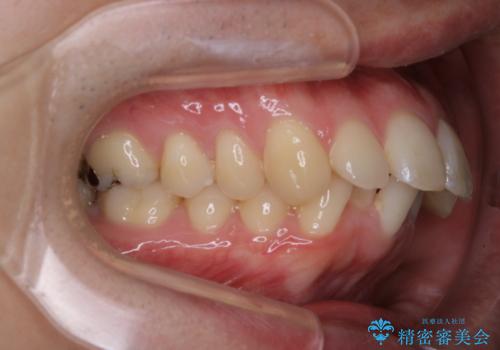

がたつき、口ゴボ(出っ歯)、真ん中のずれを抜歯矯正治療で治す。ワイヤー矯正治療

- 口元の突出感とがたつきを気にして来院されました。

突出感とがたつきの改善を行うために大きなスペースが必要であったため、親知らず以外の歯を4本歯を抜歯する計画を立てました。